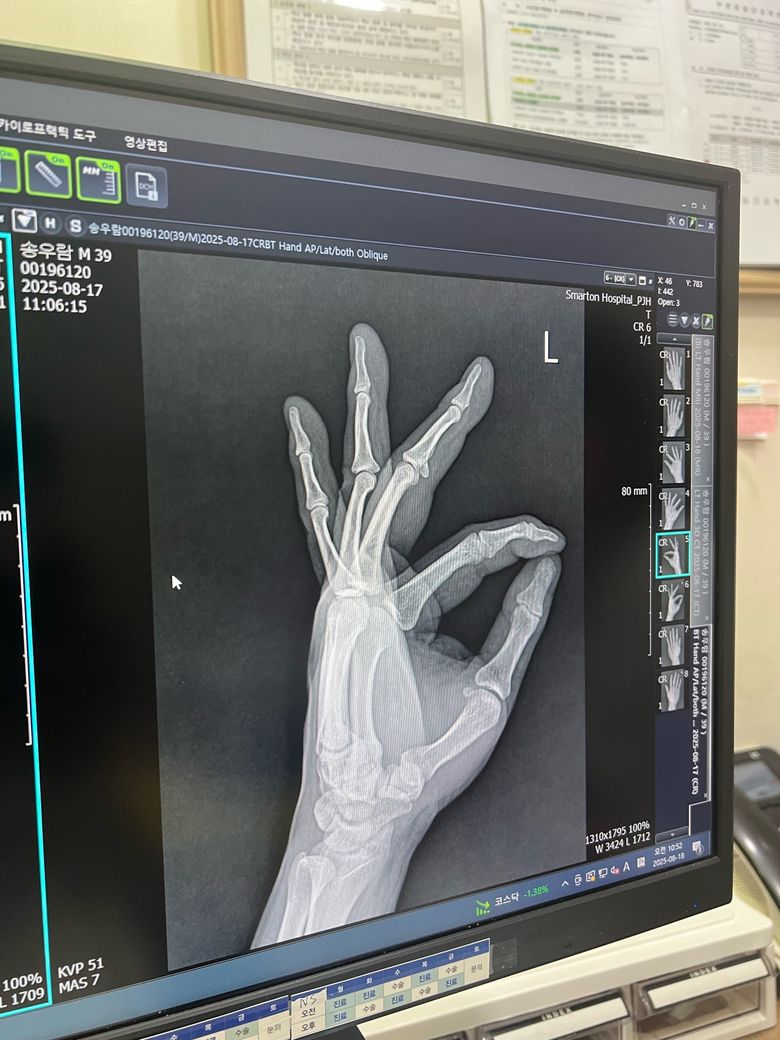

수술 전과 후 엑스레이 사진인데 잘 된건가요?

수술 이후에 초기에는 크게 변화가 없을 수 있고, 시간이 지나며 점차 회복이 이뤄지는 과정에서 변화될 것으로 생각합니다.

우선 핀을 박더라도 바로 뼈가 붙는것은 아니고 4주정도의 시간이 필요하며 정기적으로 병원에 내원하셔서 골절이 잘 유합됐는지 검사를 하시길 바랍니다.